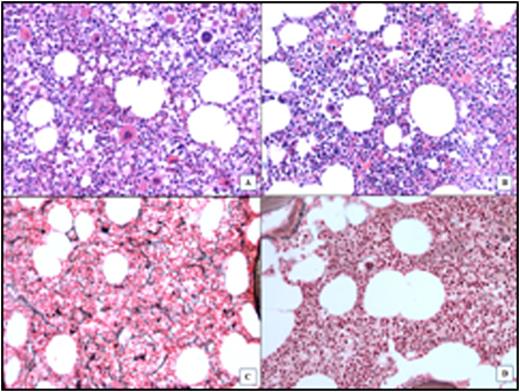

In total, 29 evaluable patients (50%) had BM response, including 13 patients (22%) with BM-CR (MF-0 in 11, example in Figure 1). Among 16 patients with BM-PR, 3 had resolution of dense collagen bundles as well as decreased reticulin fibrosis. Except for increased platelets in those with BM-PR (p<0.001), likely due to the higher proportion of ET patients in that group, no other differences in basic demographic or clinical parameters were present among different response groups (Table 1). Patients with BM response (PR & CR) had lower discontinuation rate, higher duration of response (HR & MR) with longer time on therapy; 13 patients with BM-CR had higher probability of complete MR (Table 1). Median time to BM-CR was 48 months (range, 30-72), median duration was 30 months (24-52), and has been maintained in 9 patients (69%). Two patients who lost their BM-CR are still on active therapy with persistent complete MR. Interestingly, 4 patients achieved BM-CR after being off therapy for a median of 18 months (range, 2-30), and 3 of them have sustained the BM-CR for 24, 50 and 52 months.

BM assessment of a PV patient with BM-CR. A & C: Before treatment: increased cellularity and abnormal megakaryocytes number/morphology; MF-2. B & D: After treatment: normocellular BM, normal morphology, MF-0.